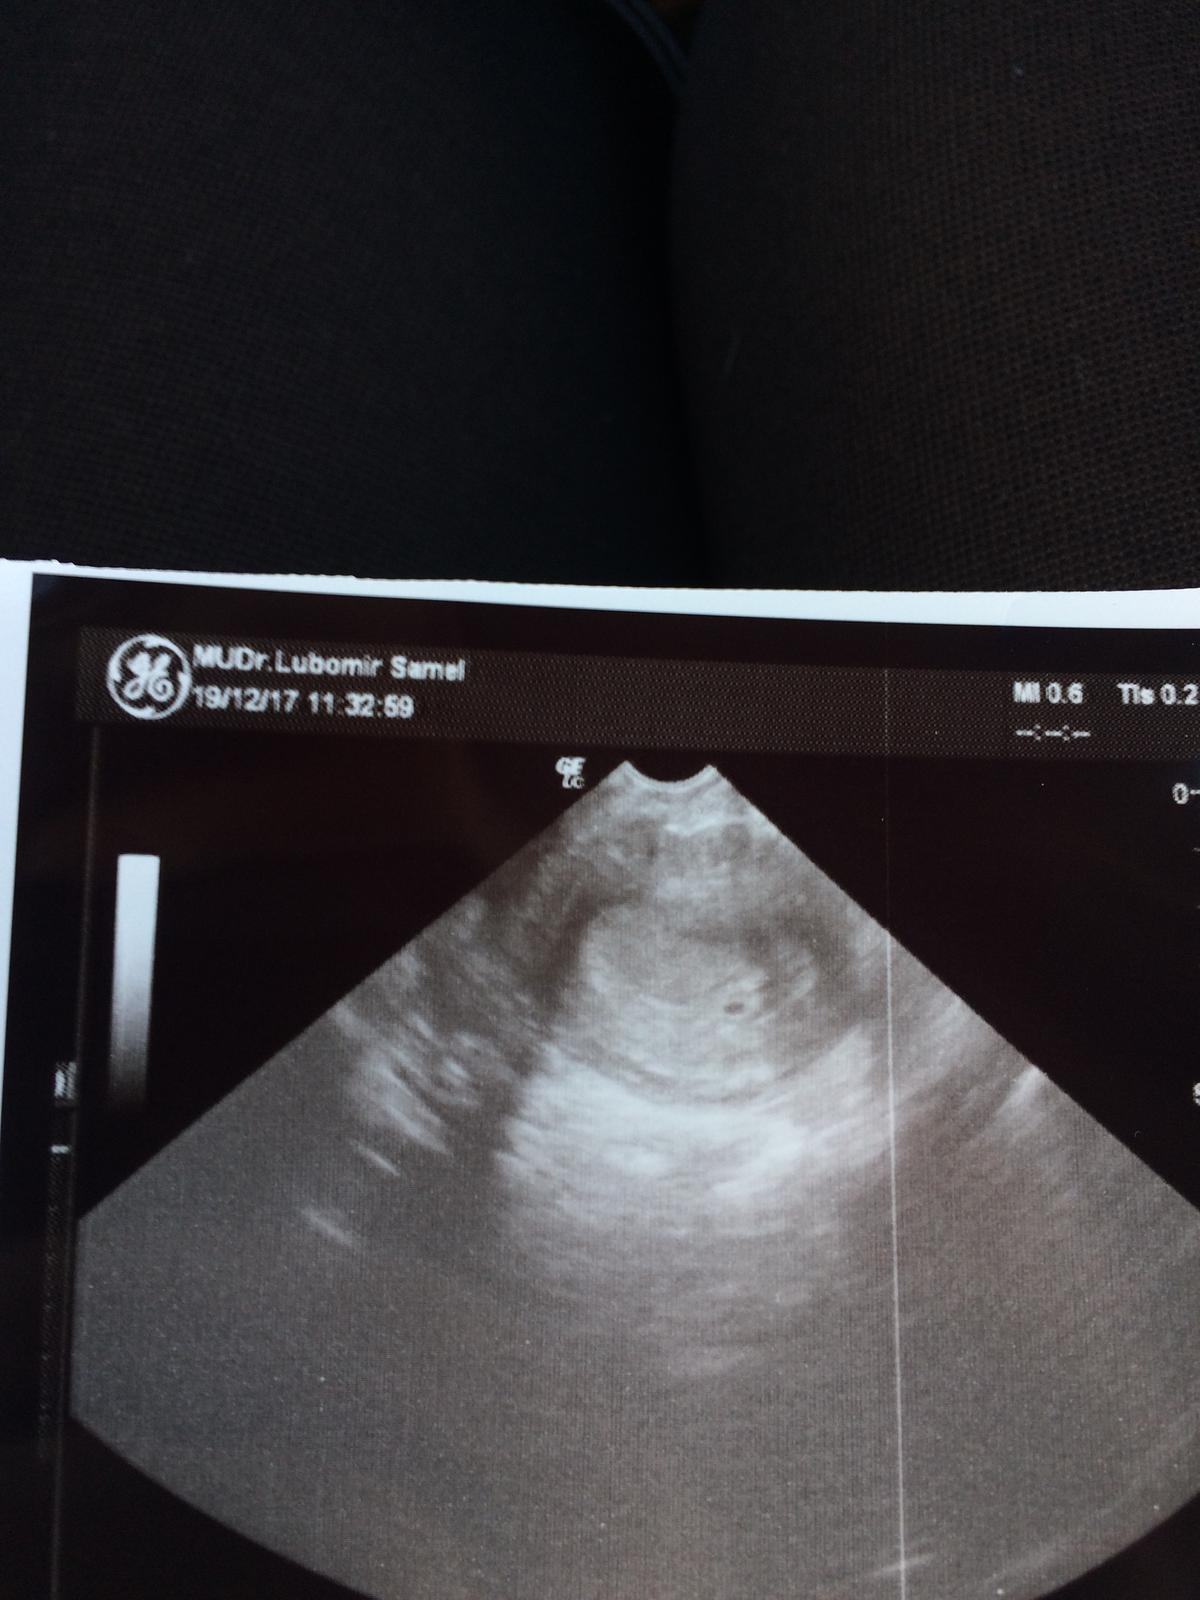

Baby bola som u lekara dal mi duphaston na udržanie a nejaké kvapky na krvácanie ... co ma znepokojuje je , ze teraz som v 5+6 ale kedže som mala posunutú ovu mi to vychádza na 4+6 ale dr na ultrazvuku videl iba dutinku ale žiaden zltkovy vak ani plod :( mám sa báť ? Bojím sa baby strašne

Gratulujem 🙂 kolky si tt ak sa možem opýtať ? Lebo dnes som bola ja tiež na sono lebo ráno som spinila a videl tam len dutinku ale žiaden zltkovy vak ani plod :( ja som 5+6 ale ovu bola neskôr tak skôr 4+6